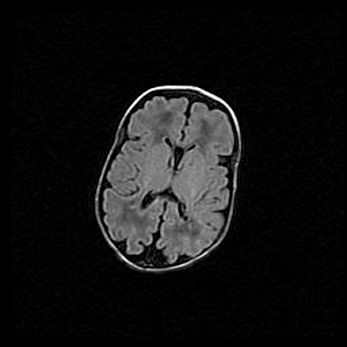

Наружная гидроцефалия с возможной атрофией височных областей.

Возраст: 28 дней

Вес: 3670 г

Пол: мужской

Окружность головы: 38 см

Срок гестации: 40 недель

Гидроцефалия головного мозга у новорожденных – это заболевание, которое характеризуется скоплением избыточного количества спинномозговой жидкости в желудочковой системе головного мозга в результате затруднения её перемещения от места выработки к месту поглощения в кровеносную систему или вследствие нарушения абсорбции. При открытой наружной форме гидроцефалии у новорожденных расширяются и переполняются субарахноидные пространства.

При нормотензивных  формах,  которые,  как  правило,  являются  следствием  перенесенных ишемических  повреждений  паренхимы  мозга,  возможно  сочетание микроцефалии  с нормотензивной гидроцефалией. В основе данных изменений лежит атрофия больших полушарий с преимущественной  локализацией  в  лобно-височных  областях.